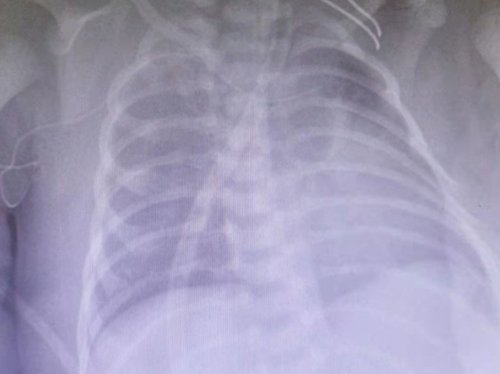

文章插图

术后复查胸片,纵膈内气体明显减少